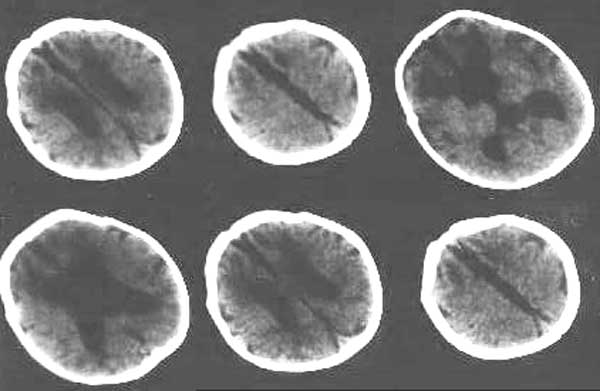

孩子一个月  体重减少700克 家里没钱治疗 只做了ct,医院建议放弃治疗

小孩以脑萎缩为主,请问是正常产吗

脑组织广泛密度减低,以白质为明显,其中又以双侧额叶白质呈囊性改变,且与扩大的侧脑室相贯通,考虑:1、严重缺血缺氧性脑病;2、脑先天发育异常。

请上传这提供生产史及病情,诊断才有科学行.凭感觉考虑:脑先天发育异常.

严重缺血缺氧性脑病脑室和脑沟不会有如此宽大吧.因为脑缺氧要造成脑水肿,脑室和脑沟应当变小.

向你的朋友表示慰问,节哀顺便吧,该患儿额叶皮质变薄,脑沟加深,应该是脑先天性发育异常。在现今社会,生存代价太大。